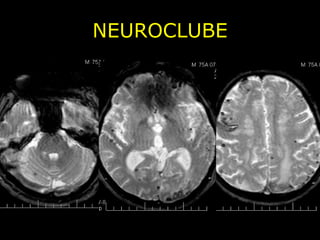

NEUROCLUBE CASO 2

NEUROCLUBE